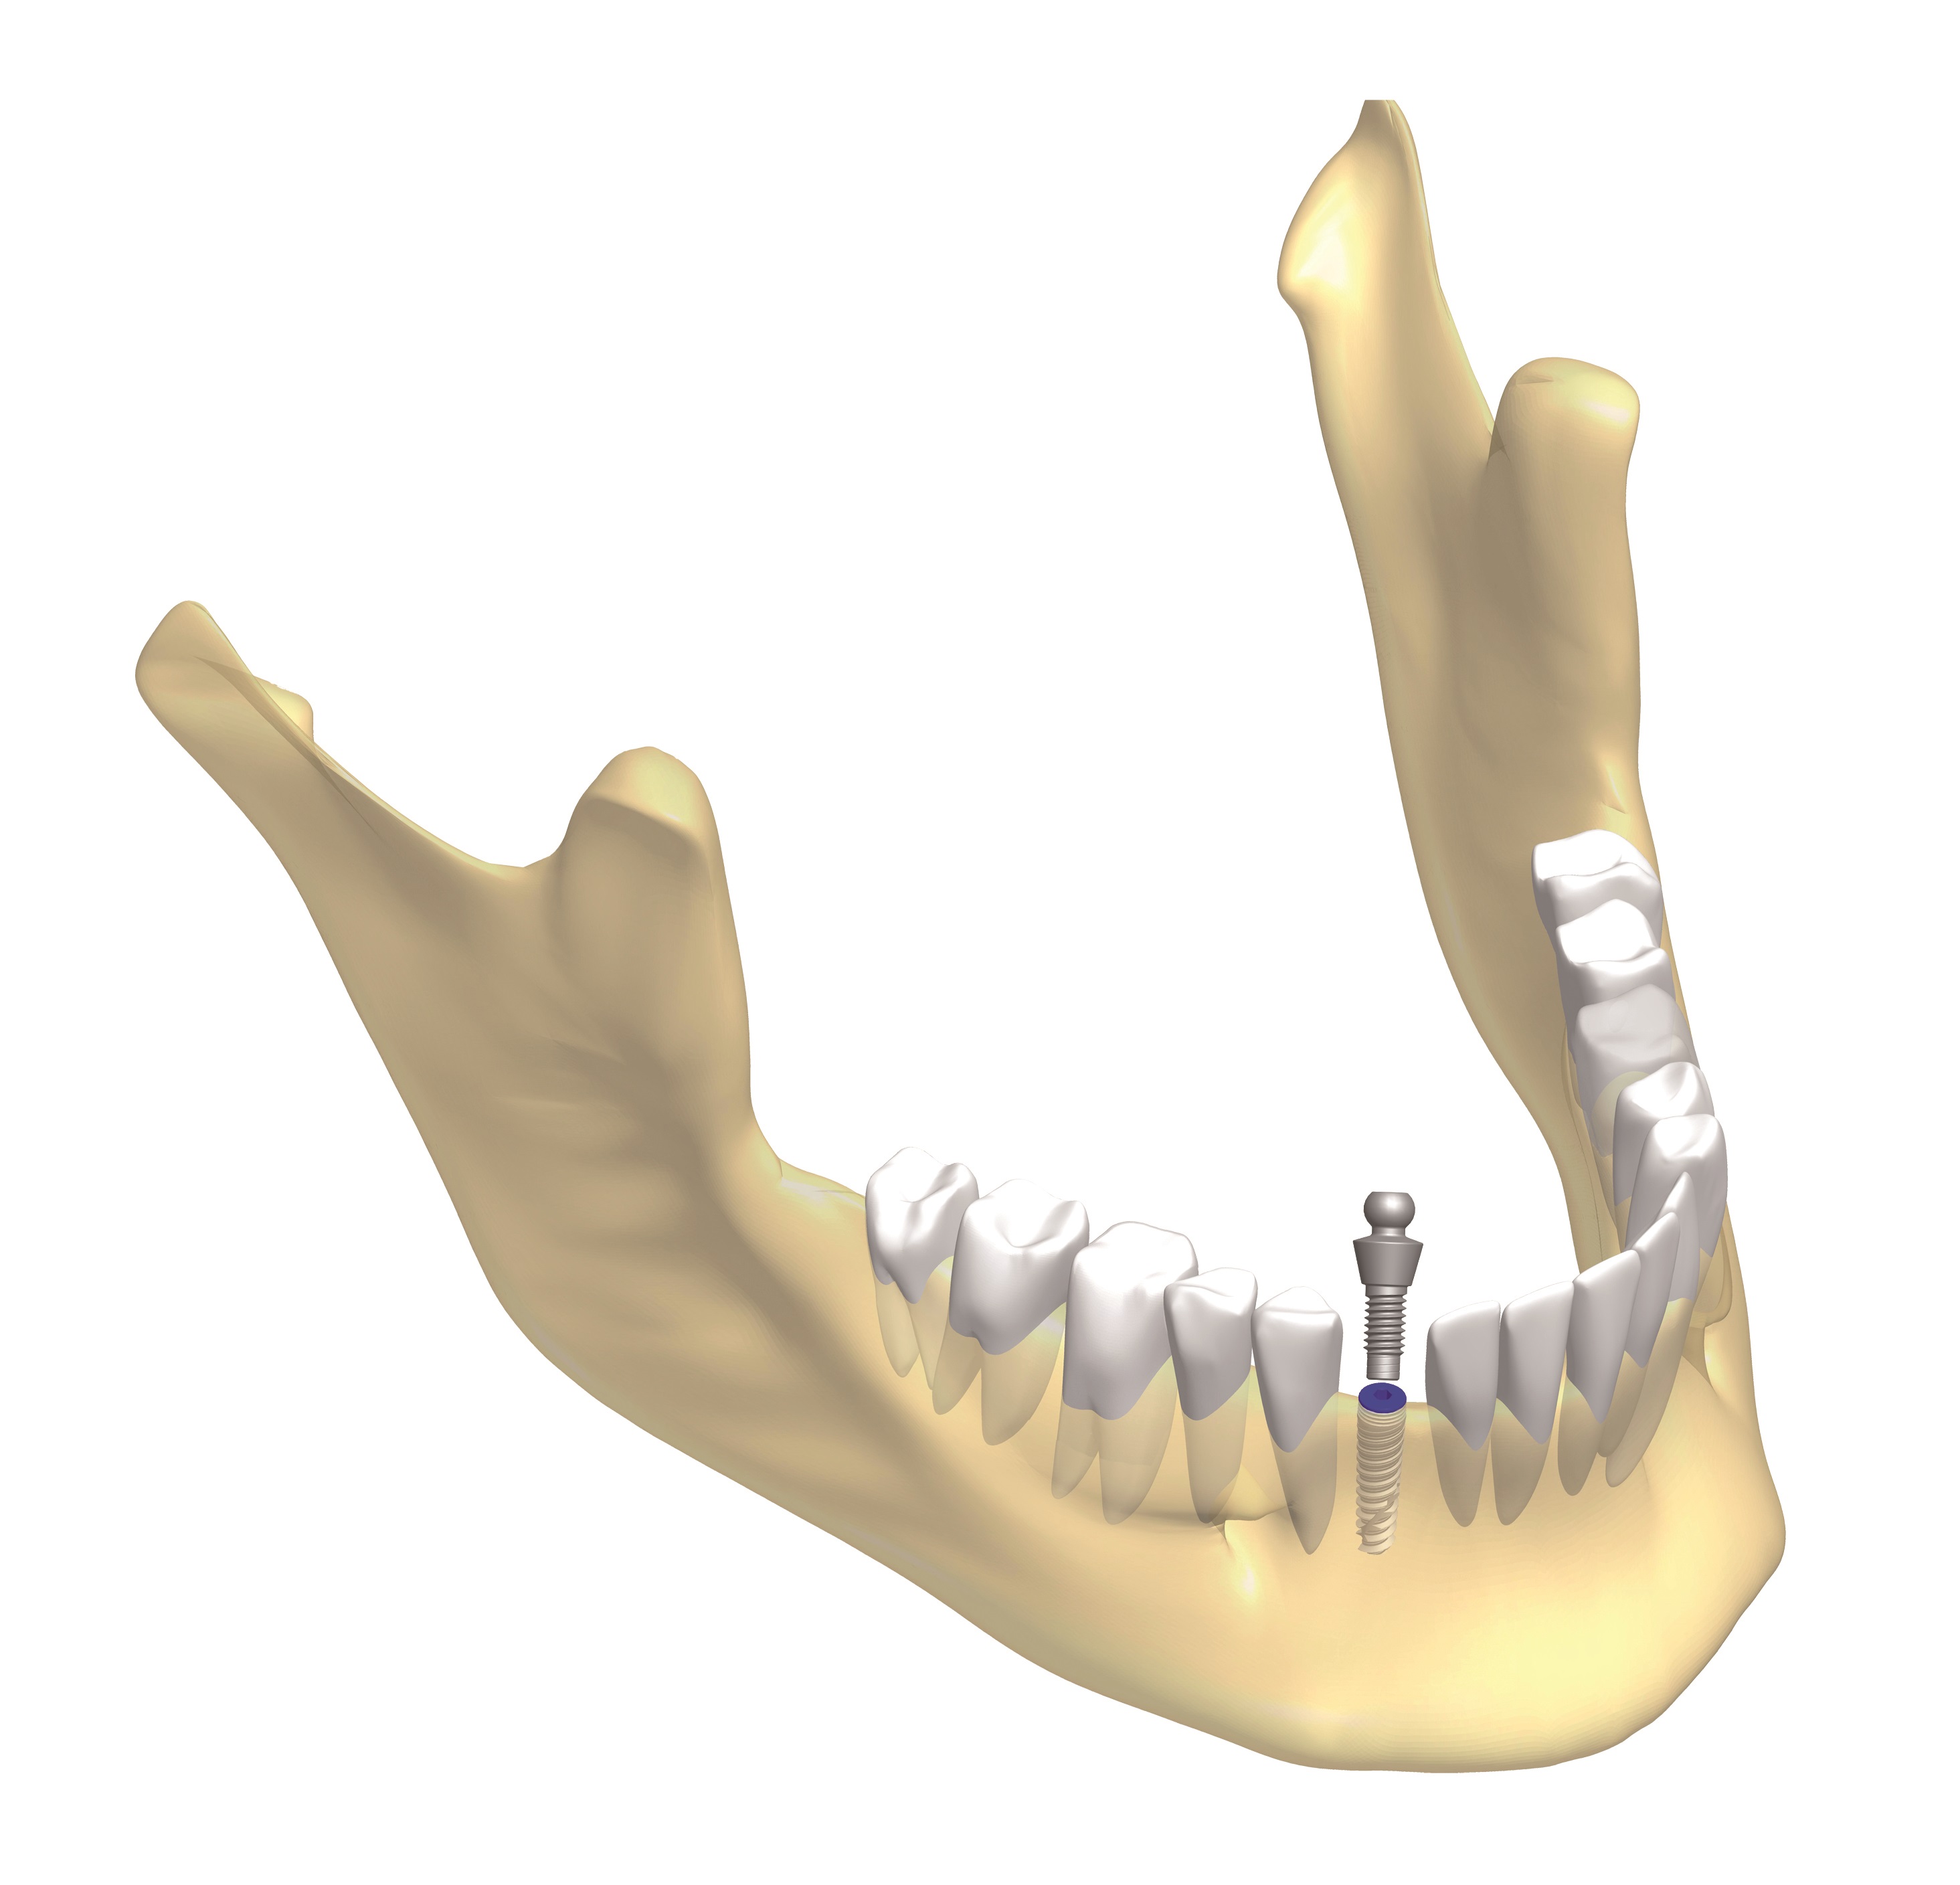

4. Ezután a nyálkahártya zárása következik. A varratokat általában 5-7 nap elteltével távolítják el. A gyógyulási vagy csontosodási szakasz kb. 3-6 hónap, ez idő alatt az implantátum felszínén található mikropórusokba belenőnek a csontsejtek, ezzel stabil rögzülést idézi elő az implantátumok számára.

5. A korona ezt követően kerül felrögzítésre a fogimplantátumhoz csatlakozó titán műcsonkra.